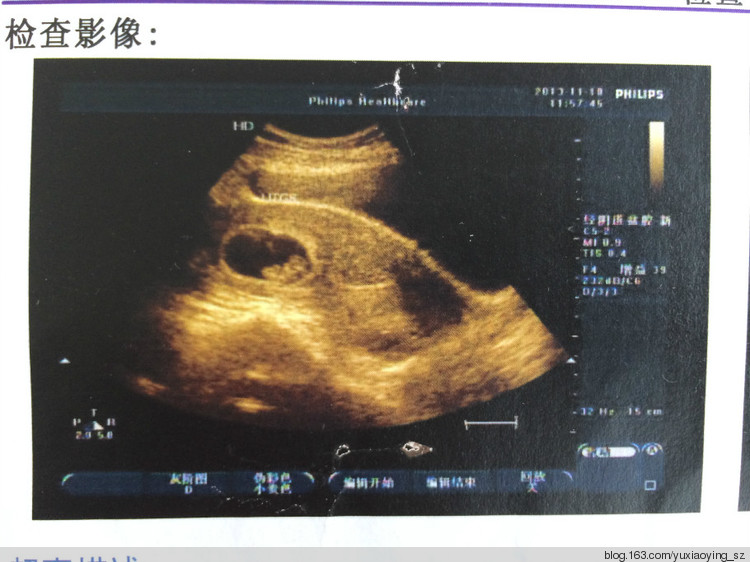

B超图像,已经能够看到你了,小衣襟。还是小小的胚芽的你,已经有了原始的心管博动,孕襄大小约为31*18mm,胚芽长4.6mm。根据大姨的归纳总结,你应该是个男孩。其实你是男孩还是女孩,都不重要,重要的是你是我们家庭中的一员,你是小天使,在不久的将来的某一个时刻,会降临在我家。

又去照了B超,孕襄大小约为42*28mm,胚芽也长长为22mm了。

通过B超图像,小小的你,已经有了模样,引发妈妈的无限暇想。

在北大医院预约了三维结构彩超,透过电视机的大屏幕,隐约的看到了小衣襟的脊柱、心脏的收缩、还有脸部。打印出来的结果上有三张图,最后的这一张,我觉得是小衣襟的脸。从脸型上看,与哥哥刚出生的时候非常相像。兄妹的缘,此时已经开始呈现。

五姨找到熟人,带着妈妈专门去照了一次B超,塞了一只大大的红包,且被自以为是的医生无故地抢白了一番,证实了你确确实实是一个女孩。大家都说女孩好,而妈妈则有些担心,你会不会是一个爱哭的女孩。

爸爸回老家了,为姥爷过世三周年祭。哥哥生日这一天,妈妈一个人去屯门医院做产检,照了B超,与大小体重有关。又问了问医生性别,又一次证实了小衣襟是女孩的现实。

小衣襟的体重有三斤多了,头在下面,手在左下腹,屁股在右上,难怪你动的时候,基本上位置都不会变呢。医生说小衣襟是个“中码”的胎儿,大小体重都合适,如此保持下去,顺产的可能性极大。而对于妈妈这个高龄孕妇来说,虽然很想体会一回做真正的女人的生产感觉,但还是信心不足,估计十有八九还是会选择剖腹产。

又去照了一次B超,医生指给妈妈看小衣襟的头、屁股、手和脚,还有心脏的跳动。其实妈妈不需要看这些,也知道小衣襟的样子,因为每天每天,小衣襟都在妈妈的肚子里练跳舞练拳脚,无时不在提醒妈妈你的存在和活泼健康。小衣襟的体重已经有2.1公斤重了,较三周前增加了0.6公斤,照这样的速度下去,到出生的时候,至少会达到3公斤。女孩,这样的体重应该可以了,先给小衣襟发个达标奖状好了。